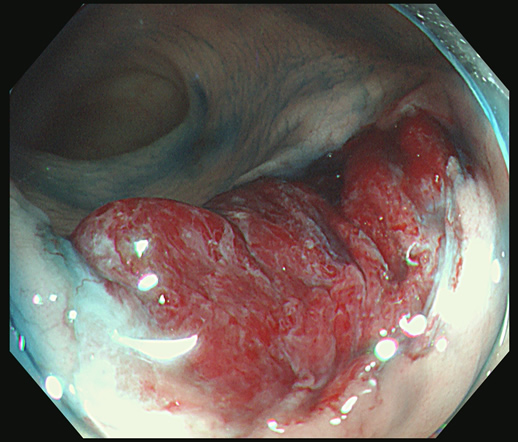

前項で述べましたように「不完全切除」は良く起こる現象で、しばしば「内視鏡後・大腸癌」の原因になります

患者さんは、「ポリープ切除後の写真」をしっかり確認することが重要です。